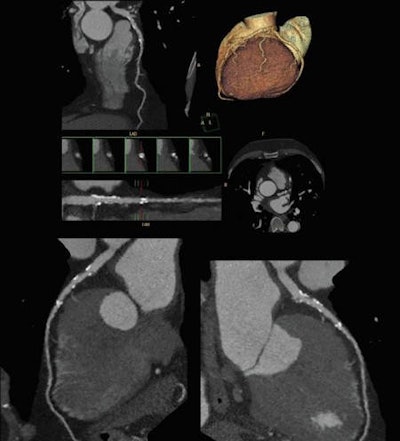

Looking at an occlusion with angiography, you have no idea about what is going on behind that occlusion, but CT can visualize the amount of plaque and also the coronary lumen, according to Achenbach. With a high negative predictive value consistently ranging between 98% and 99% in different studies, CT allows cardiologists to confidently rule out stenosis, giving it a high prognostic value. The modality has a close-to-zero event rate after ruling out stenosis, allowing 84% of patients to be sent home without a single recorded cardiac event among this population over the next 30 days.

CT has lower spatial resolution than invasive angiography, such that severe calcifications can become a problem. Temporal limitations can make motion problematic, requiring a breath-hold and even still producing artifacts within the image due to natural heart movement.

The angiography image may seem misty and blurred, but it shows the whole picture, with a synthesis of all layers of the heart immediately available, Meier commented. It may be old and not fancy, but angiography provides information CT cannot give, such as hemodynamics and flow patterns, and pressure grades can be measured with catheterization, he said.

"The dismal specificity of CT means you are going to have concerns where there is nothing wrong," Meier said. "CT images actually tend to overestimate problems, sometimes dramatically, and you need to look inside the artery to know if there is a clinical significance."